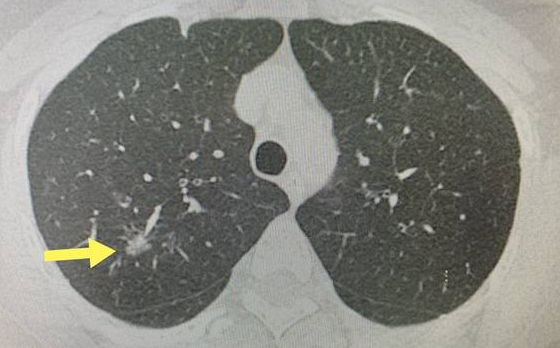

磨玻璃结节是指CT影像上表现为边界清楚或不清楚的云雾状密度增高影,其增高的密度尚不能掩盖肺里面的血管和支气管。样子看起来像病变的肺部蒙上一层磨砂玻璃,故而叫磨玻璃结节。其中包含有实行成分又有磨玻璃密度的结节为混合磨玻璃结节。

在《肺部结节的诊断及处理进展》里指出单纯性磨玻璃样肺结节(pGGN)的恶性比例可达59%~73%,伴有实性成分的GGN(mGGN)恶性比例可高达80%以上。也就是肺结节中磨玻璃结节是恶性的比例更高,而表现为磨玻璃结节的肺癌往往是早期,大部分患者切除后可以达到治愈并长期生存,符合肿瘤的早诊断、早治疗,所肺磨玻璃结节在临床上被高度重视。